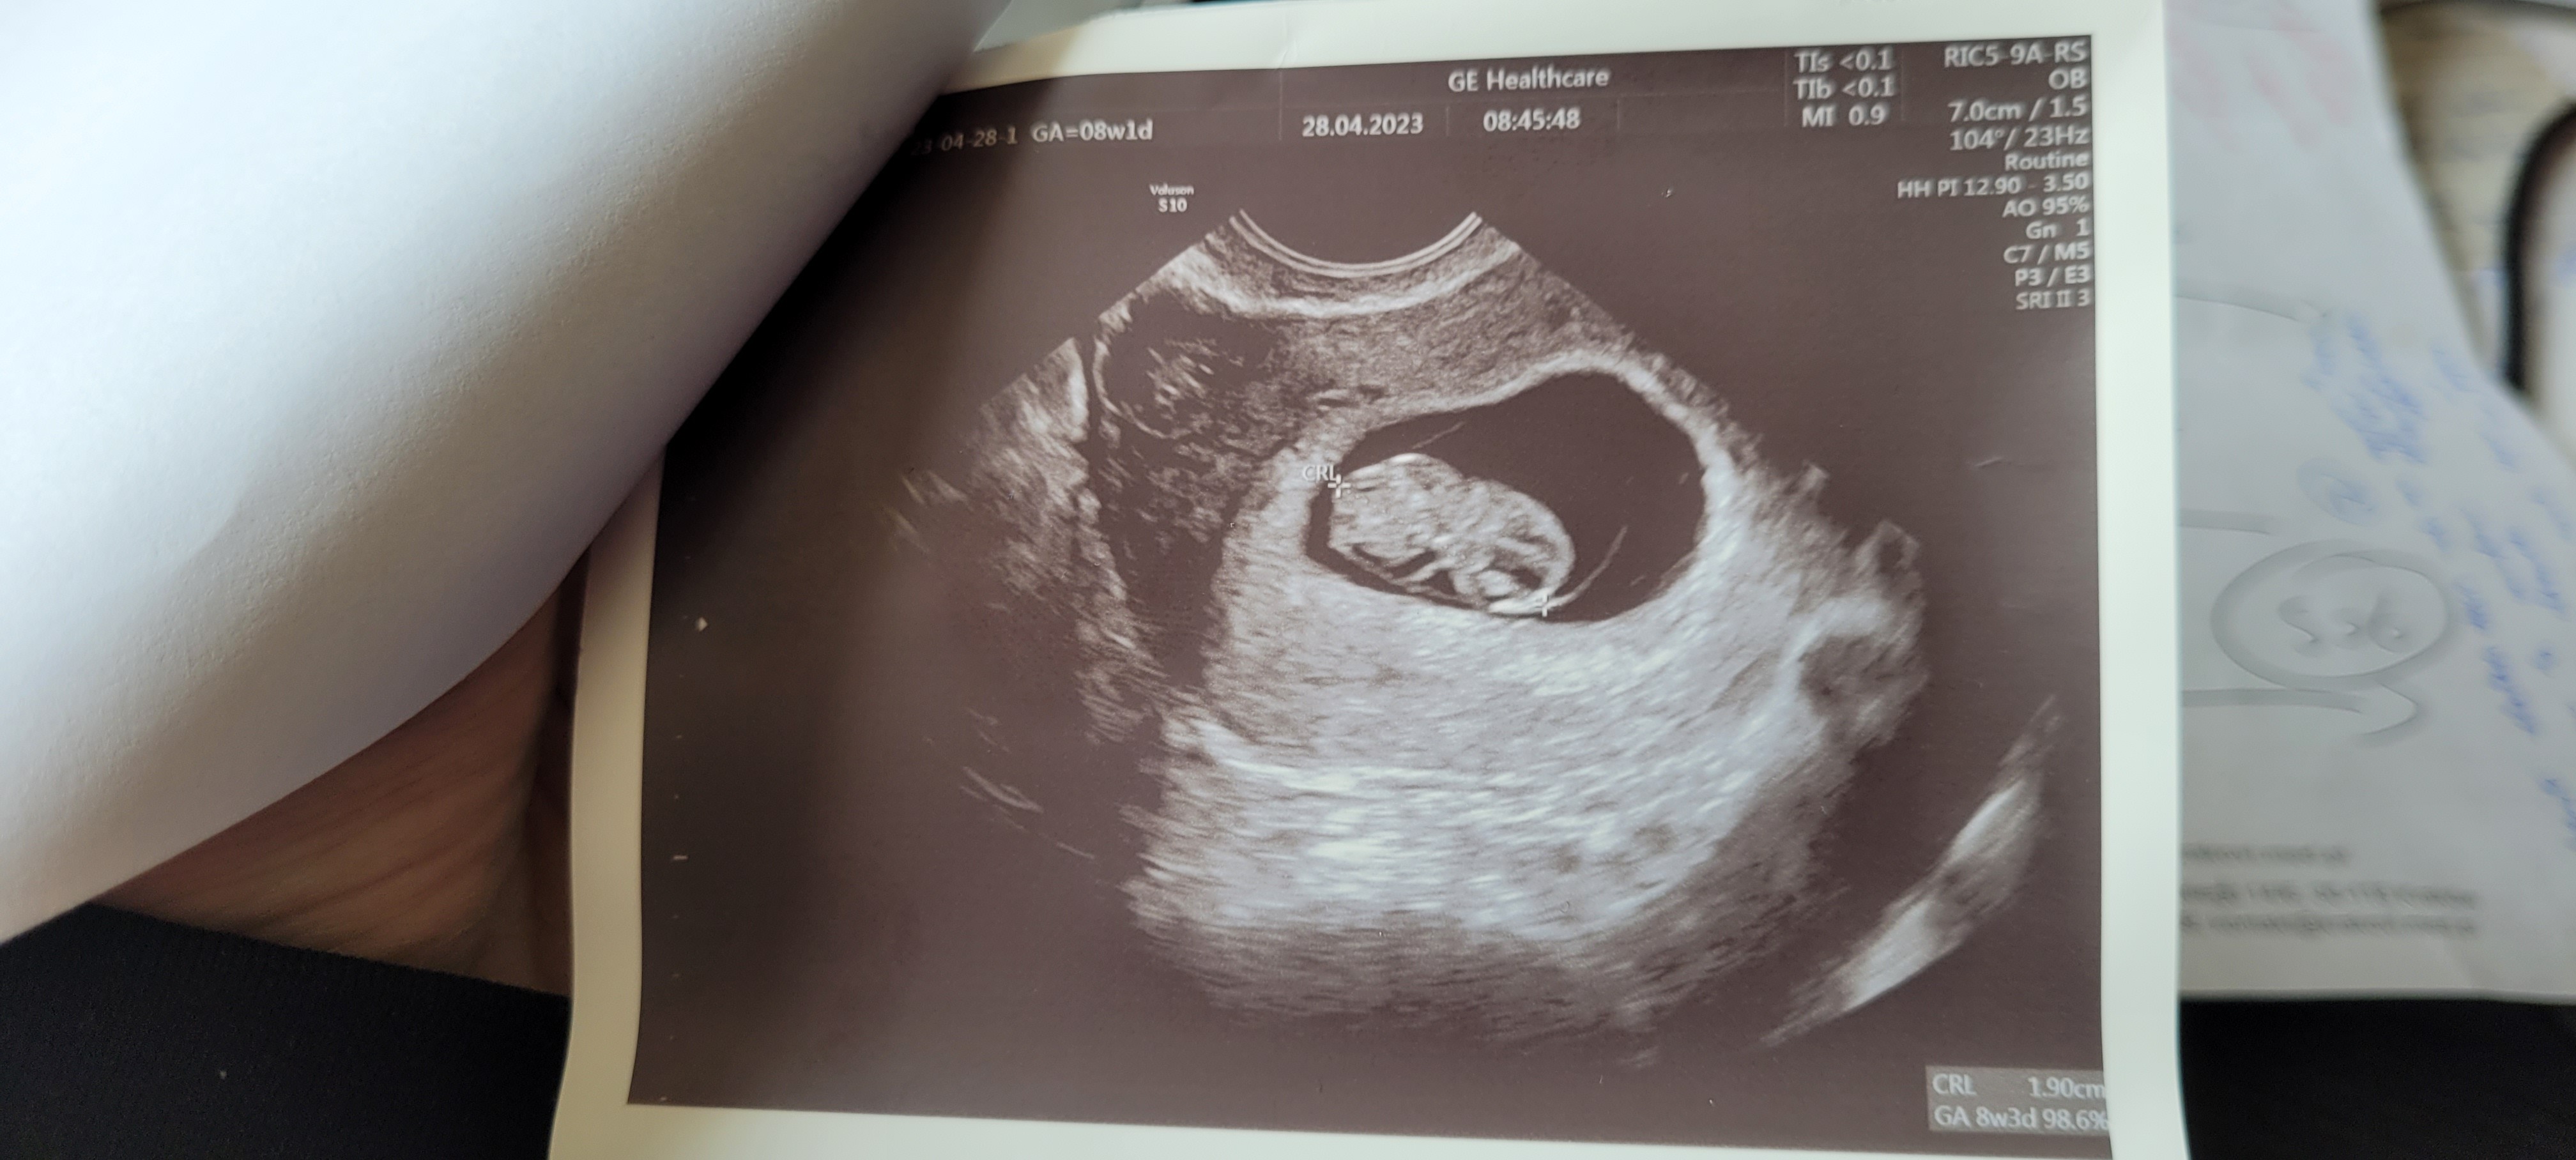

u nas z krwią tak samo, dzięki ze informujeszHej dziewczyny! Ja już po dzisiejszej wizycie i wszystko dobrzeDzisiaj jest 8 + 1 a wg USG 8 + 3. Zarodek ma już 1.9cm. Serduszko ładnie bije

termin porodu zmieniony na 7 grudnia.